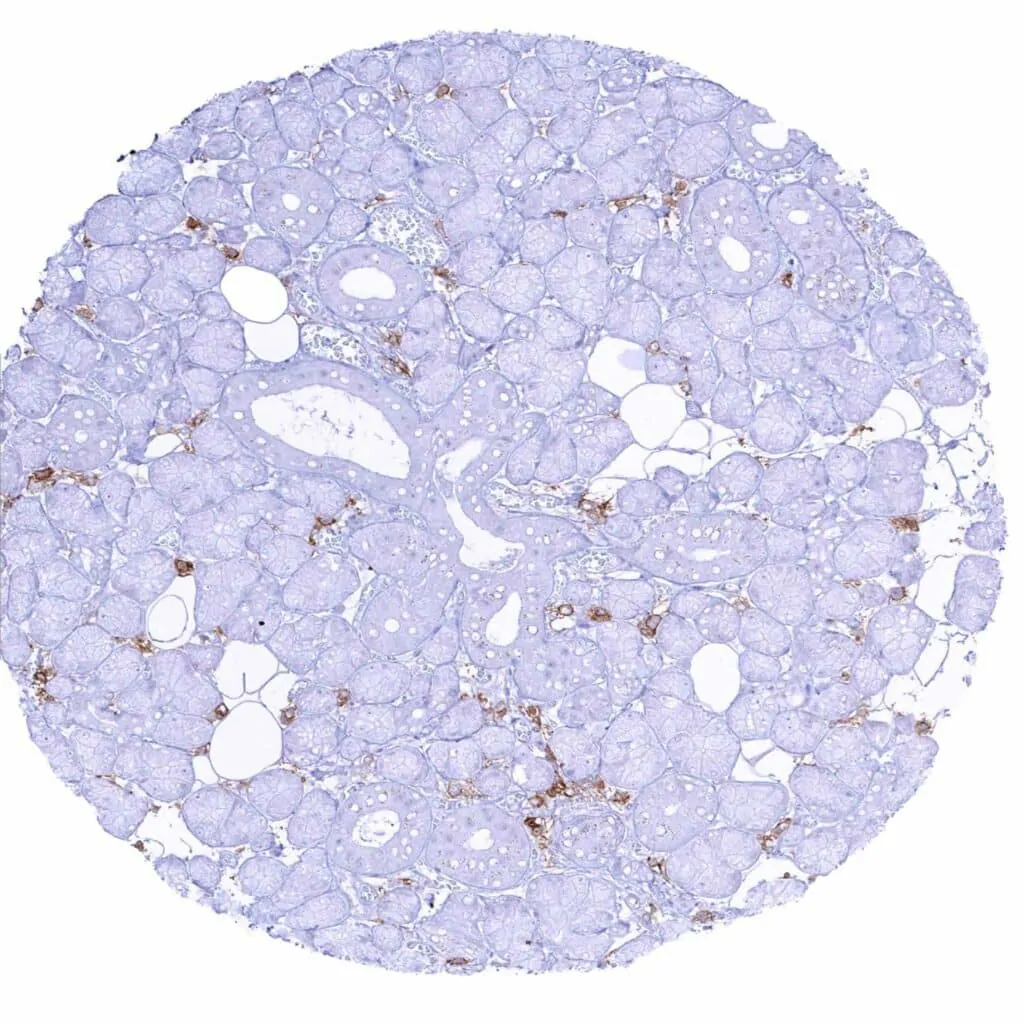

Thyroid gland